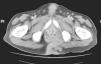

The patient is a 52-year-old male with an anal tumor that had been progressing for the previous 6 months. The patient reported a weight loss of 20kg, pain and local bleeding. Upon exploration, a 20cm×18cm exophytic mass was observed at the anal margin, which was ulcerated and discharged a purulent liquid (Fig. 1). Computed tomography revealed an extensive pelvic mass, with no infiltration of the rectal wall (Fig. 2). Abdominoperineal amputation was performed, followed by radiotherapy. The pathology results defined the lesion as a giant condyloma acuminatum, or Buschke–Löwenstein tumor. Two months after surgery, the patient presented local recurrence with rapid deterioration of his general condition and died within a few weeks.